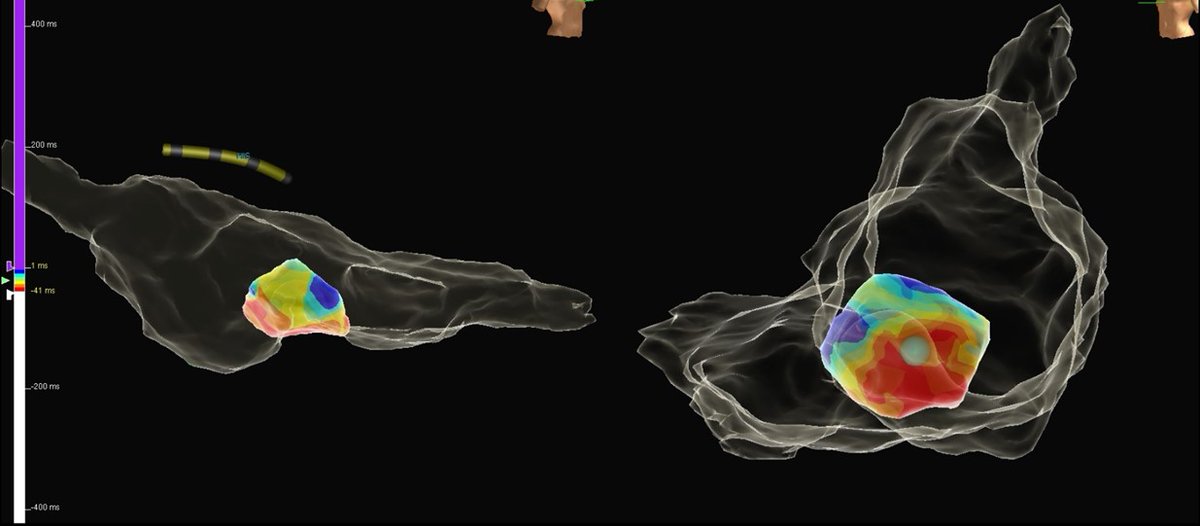

Micro-reentrant AT in the anterior LA during persistent AF ablation following PVI, anterior mitral isthmus and roof lines. All EGMs of the Pentaray (yellow circle) encompass the TCL. Focal ablation in this area terminated the AT. #HowcoolisEP #HDmapping